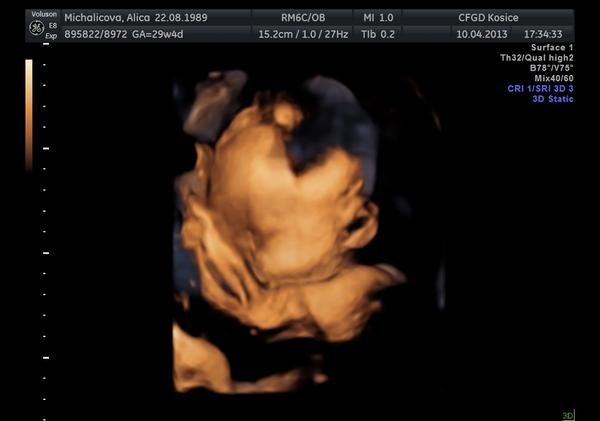

ahojte baby, tak máme za sebou 3D ultrazvuk som sa tešila že uvidim tváričku malej ale potvorka sa celý čas zakrývala ručkami tak vela toho nevidno 😀 ale nevadí no, hlavne že je všetko v poriadku má okolo 1550g... nezdá sa vám to vela na 30.tt?neviem to porovnať lebo pri prvej dcerke som nebola na 3D. Pekný dník prajem ešte pridám 2 fotky :o)